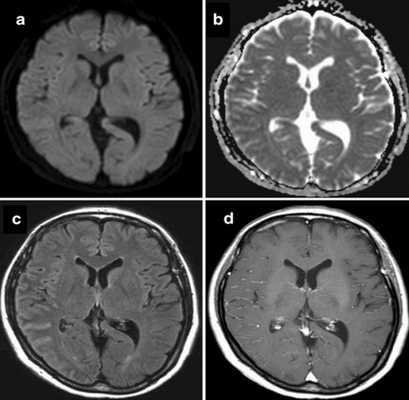

Ревматоидный менингит с инсультоподобными нарушениями на МРТ: DWI (a), карта ADC (b), FLAIR (c), T1 ВИ с контрастом (d)

При менингите развивается воспаление в мозговых оболочках, сопровождающееся утолщением последних, нарушениями тока ликвора, экссудацией, расширением борозд и межполушарной щели и другими неспецифическими изменениями. Сканирование с контрастом показывает характерное окрашивание очагов воспаления и патологического выпота. МРТ после менингита дает информацию о наличии или отсутствии осложнений, позволяет оценить полноценность восстановления мозговой ткани.

Рентгенологи проводят расшифровку снимков, исходя из интенсивности сигнала от определенных тканей при применении разных режимов сканирования. МРТ-признаками менингита считают:

- изоинтенсивный ответ от экссудата на Т1 ВИ;

- гиперинтенсивный сигнал от тех же зон на Т2 ВИ;

- признаки гидроцефалии или повышение интенсивности импульсов от борозд и цистерн;

- характерное окрашивание структур, окружающих гнойники, после контрастирования;

- гиперинтенсивный сигнал от абсцессов, визуально заметная капсула;

- сужение просвета артерий или окклюзионные изменения при ангиорежиме сканирования;

- тромбоз вен при магнитно-резонансной венографии.